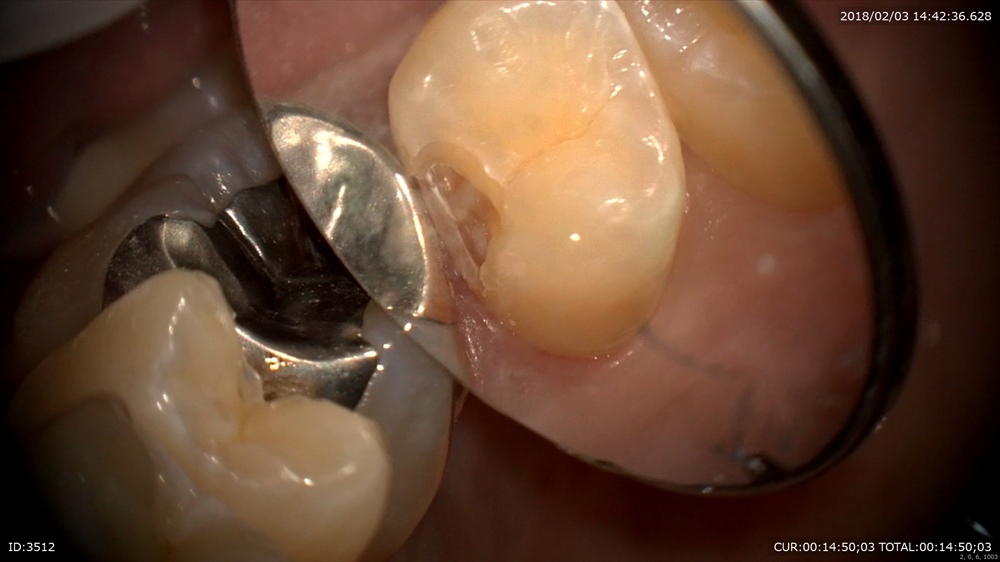

次はこの虫歯

歯と歯の間

すごいね。丁寧に感染を染め出して

MTAセメント

歯と歯茎の境目をどうして出血もなく痛みもなく削れるか。

これは患者さまから良く聞かれます。

「他の歯医者だったらいつもうがいする所に血がつくけど先生の所はないわ」

理由は2つあります。僕が上手いから笑といいたい所ですが腕は普通です。

①虫歯治療の前に必ず歯周基本治療をしているから歯茎がしまっています。

②マイクロスコープをこの様に↓

ここをズーム

25倍

この制度で研磨するので歯茎さわりません。

だから痛みがないし血はでません。

この精度 血がでないでしょ。だから術後も楽~